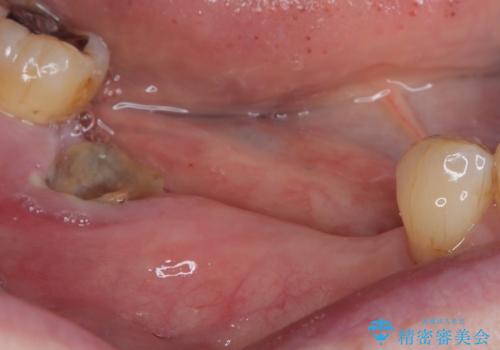

仮歯を速やかに撤去して力が一切かからない状態とし、1か月後と2か月後にそれぞれ安定値を測定することしました。

2か月後には無事に値が回復したため、セラミッククラウンにて補綴治療を行いました。